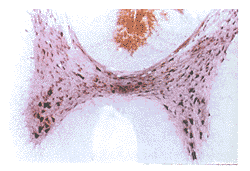

正常组、对照组T7~8灰质神经元胞浆内可见淡紫蓝色阳性颗粒。前角Ⅸ区大多极神经元胞浆内着色较深。后角Ⅰ~Ⅲ区未见阳性细胞。Ⅳ~Ⅵ区及中央管周围Ⅹ区见中等量杂交阳性神经元。在非神经元细胞,包括胶质细胞和星形细胞,未见阳性信号。白质中无着色。灰质中偶见阳性血管内皮细胞表达。见图1,2。损伤组T7~8灰质中ET-1 mRNA表达明显增多,主要表现为数目增多,着色变深。非神经元细胞及白质中未见阳性表达,后角Ⅰ~Ⅲ区见少量阳性细胞表达。损伤后0.5 h即有明显表达增多,主要表现在前角(Ⅸ区)。见图3,4。经统计学处理,前角阳性颗粒灰度和面积与对照组比较有显著性差异(P<0.05)。见表1。损伤后4 h ET-1 mRNA表达达高峰(P<0.01),48 h仍有明显升高(P<0.05),至72 h趋于正常水平。正常组与对照组比较无明显差异。

图1 正常大鼠T8~9 ET-1 mRNA原位杂交结果 碱性磷酸酶法染色2.5×10

图2 正常大鼠T8~9前角ET-1 mRNA原位杂交结果 碱性磷酸酶法染色2.5×40